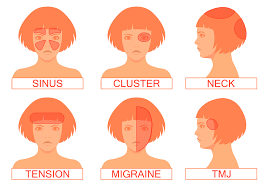

1. Primary Headaches: These are not caused by another medical condition and include:

– Tension Headaches: The most common type, characterized by a dull, aching sensation across the forehead or the back of the head and neck. Stress, poor posture, and muscle tension are common triggers.

– Migraine Headaches: Intense, throbbing pain usually on one side of the head, often accompanied by nausea, vomiting, and sensitivity to light and sound. Migraines can last from a few hours to several days.

– Cluster Headaches: Severe, piercing pain around one eye, occurring in clusters or groups over a period of weeks or months. These headaches are less common but extremely painful.

• Sinus Headaches: Caused by inflammation or infection in the sinuses, leading to pain and pressure around the forehead, cheeks, and eyes.